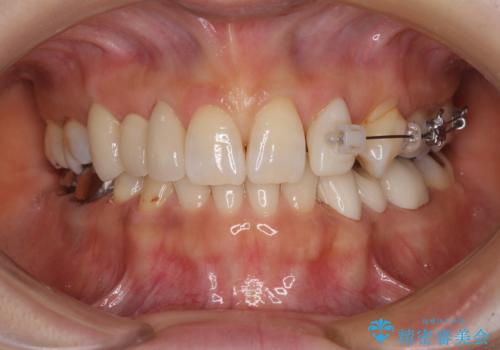

隙間が全て閉じたことで、長年食事の度に挟まる不快感が改善されました。

また、正面から見た印象がまるで自分の歯であるような自然な仕上がりとなりました。